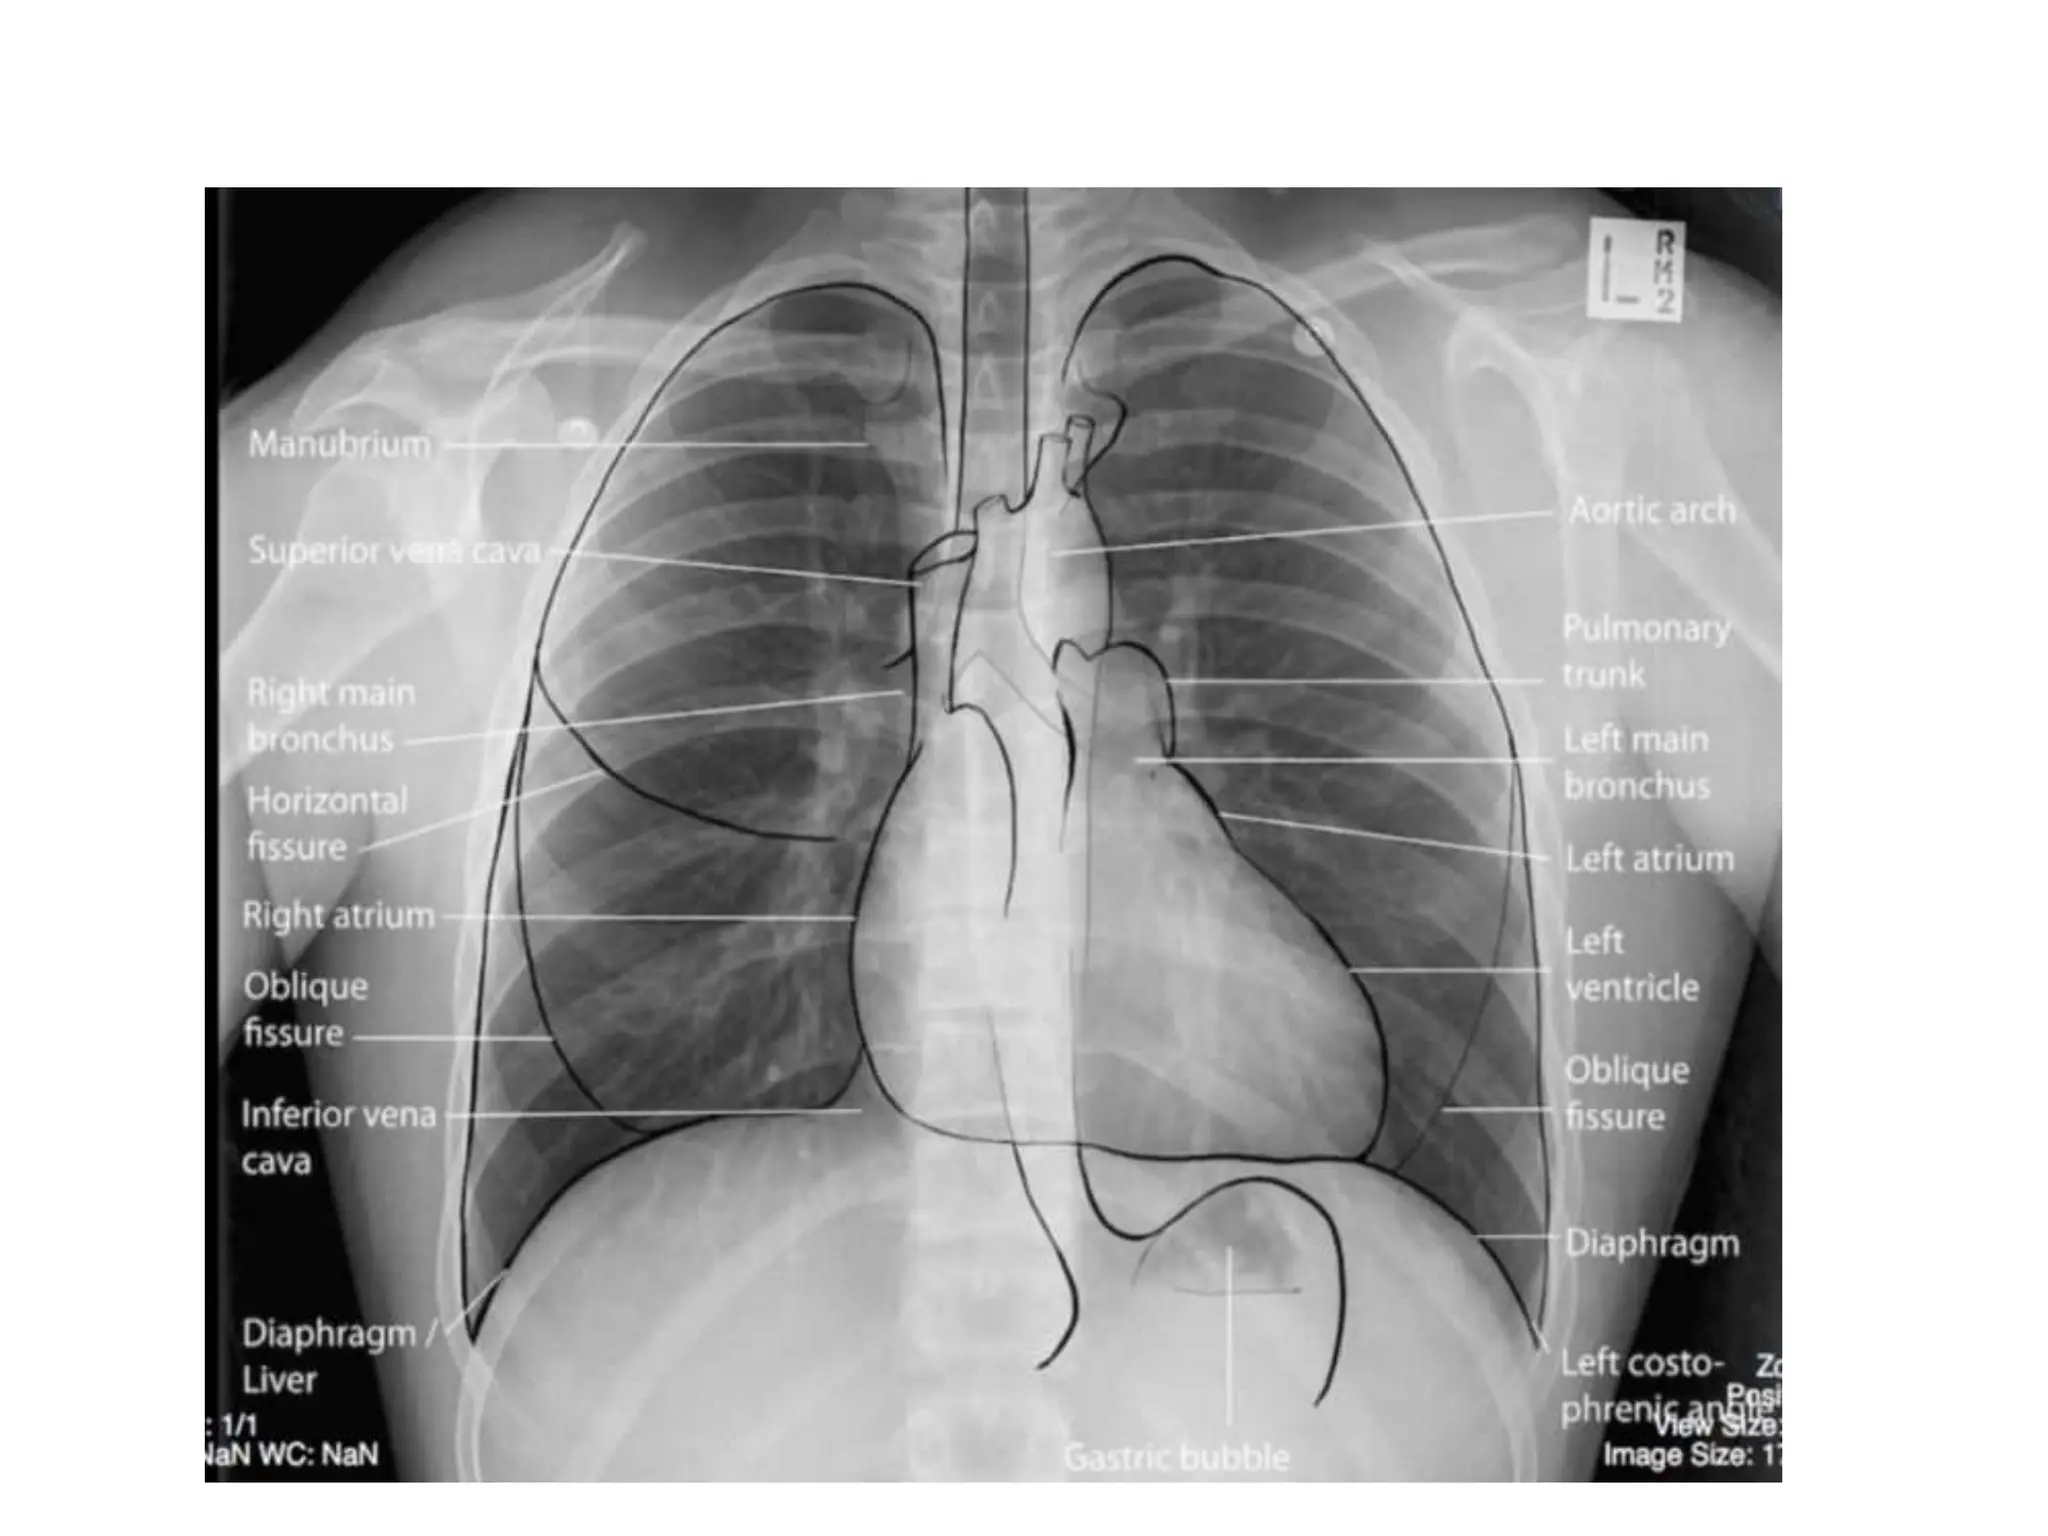

• A systematic approach for viewing chest X-rays ensures no

important structures are ignored

• Anatomical structures to check

1. Trachea and bronchi

2. Hilar structures

3. Mediastinum

4. Heart

5. Lung zones

6. Lung lobes and fissures

7. Pleura

8. Costophrenic angles

9. Diaphragm

10.Soft tissues

11.Bones